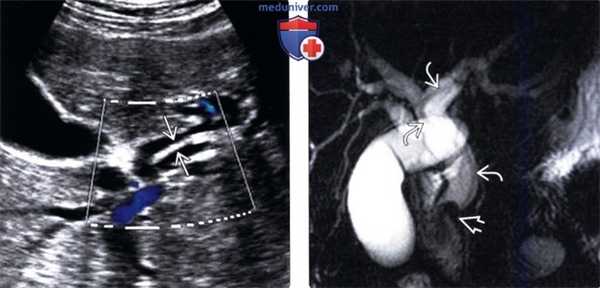

(Слева) На сонограмме (цветовая допплерография) у пациента с лихорадкой и желтухой в расширенном левом печеночном протоке определяется эхогенный дефект наполнения вытянутой формы, обусловленный наличием паразитического червя.

(Справа) На корональной МРХПГ у этого же пациента определяется расширение внутри- и внепеченоч-ных желчных протоков; в левом общем печеночном протоке (и вплоть до дистальных отделов общего желчного протока) виден дефект наполнения (аскарида). Дефект наполнения в дистальных отделах общего желчного протока, как выяснилось в конечном итоге, был обусловлен холангиокарциномой - известным осложнением аскаридоза.